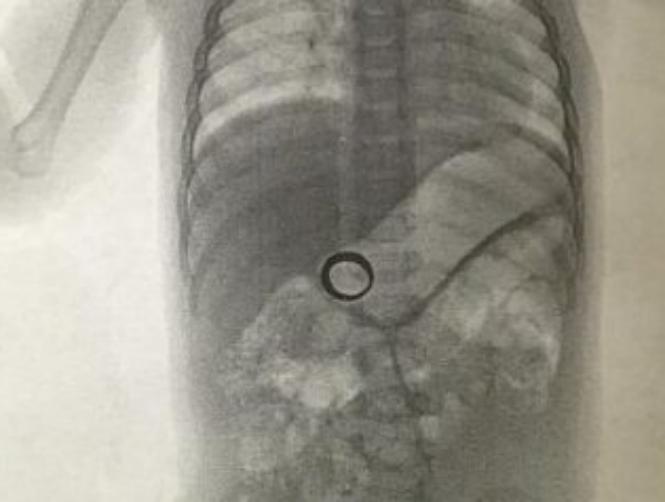

بعدما عجزت أم بريطانية عن العثور على خاتم زواجها الذي أضاعته، وهو عبارة عن "هدية زواجها"، قرّرت أن تلجأ إلى الطبيب وكانت النتيجة صادمة. فهذه الزوجة ظنّت أنها أضاعت خاتم زواجها إلى الأبد، حتى خطر لها أن تصطحب رضيعها إلى طبيب لأخذ صورة شعاعية "لقطع الشك باليقين".

وأظهرت صورة الاشعة خاتم المرأة داخل أحشاء ابنها الذي ابتلعه بالخطأ، وحظيت الصورة بعد نشرها من قبل الزوج، بآلاف المشاركات من قبل المتابعين على شبكات التواصل الاجتماعي.

وكم كانت فرحتها ودهشتها عظيمة عندما لاح الخاتم المستدير وسط صورة الأشعة بين أحشاء ابنها، بحسب ما نُشر على موقع "ميرور" البريطاني. والزوج السعيد نشر الصورة على موقع "ريديت"، حيث حظيت اللقطة بآلاف المشاهدات.